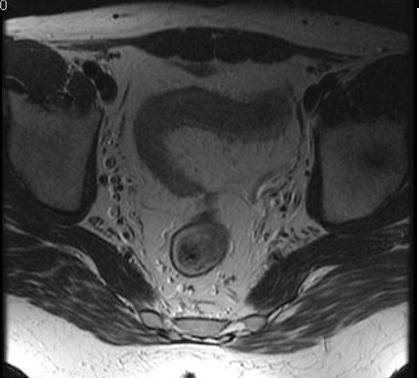

Image

radiologique IRM est l'epaissisement parietale

et cette technique c'est le bien pour localisatrice de

lesion . La T2 avec TE court peut

caracterise de l'epaissisement de paroi de l'intestin , de

la differenciation

complex muco-sous muqueux et recherche de oedeme sous muqueuse

. La T1 fatsat peut utilise pour recherche des fistules ,des lesions inflamatoires , lesions fibreuses et des pseudo-polyp

.

Image IRM en coupe axiale T1

fat sat du maladie de Crohn . Epaissisement de la

paroi du colon avec infiltration graisseuse

extramurale du colon . |